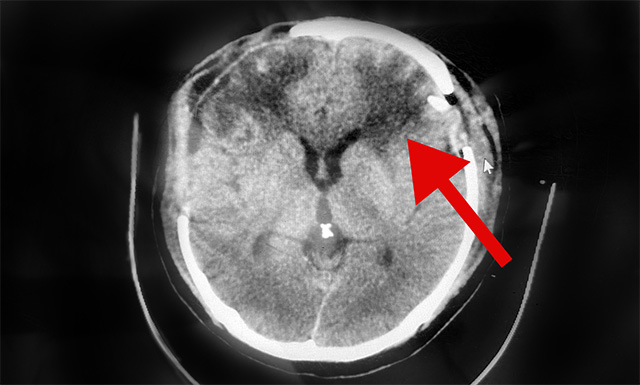

10月4日,经与神经外科6A病区侯增欣主任会诊后认为,患者赵先生右侧硬脑膜下血肿虽已清除,但CT检查显示其左侧硬脑膜下仍存在较大面积血肿,颅内压高,非常危险随时形成脑疝,必须马上手术。

▲术后CT示:患者左侧脑内血肿已清除

在明确告知患者家属手术风险并获得签字同意后,侯增欣主任于10月4日中午在全麻状态下为赵先生进行了脑内血肿清除手术。

随着穿刺针的插入,暗红色血性液体开始沿导管涌出,共引流约40ml,手术进展顺利。术后,随着麻醉苏醒,赵先生睁开了眼睛。